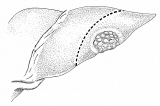

和綴じの方法を応用した、肝部分切除

和綴じの本をお持ちの方は、バラして見るのも一興かも。でも、ご先祖様が化けて出るかも